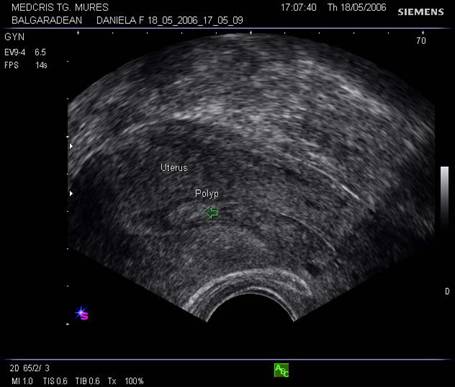

Fig. nr.368. Polip endometrial. Se remarca zona cu ecogenitate crescuta fata de restul endometrului, bine delimitata si marcata cu sageata.

Fig. nr.369. Polip endocavitar uterin in statu nascendi, la examenul clinic

Fig. nr.370. Polipul din figura precedenta la examenul ecografic vaginal, cu vascularizatia de origine endocavitara uterina la examenul Doppler, determinand dilatatia canalului cervical